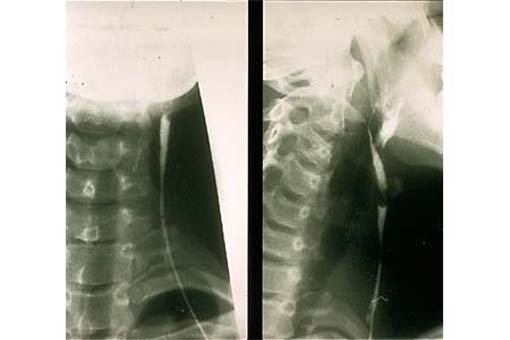

Laterale Halsfistel, Kontrastmittelaufnahme... Zum Kapitel